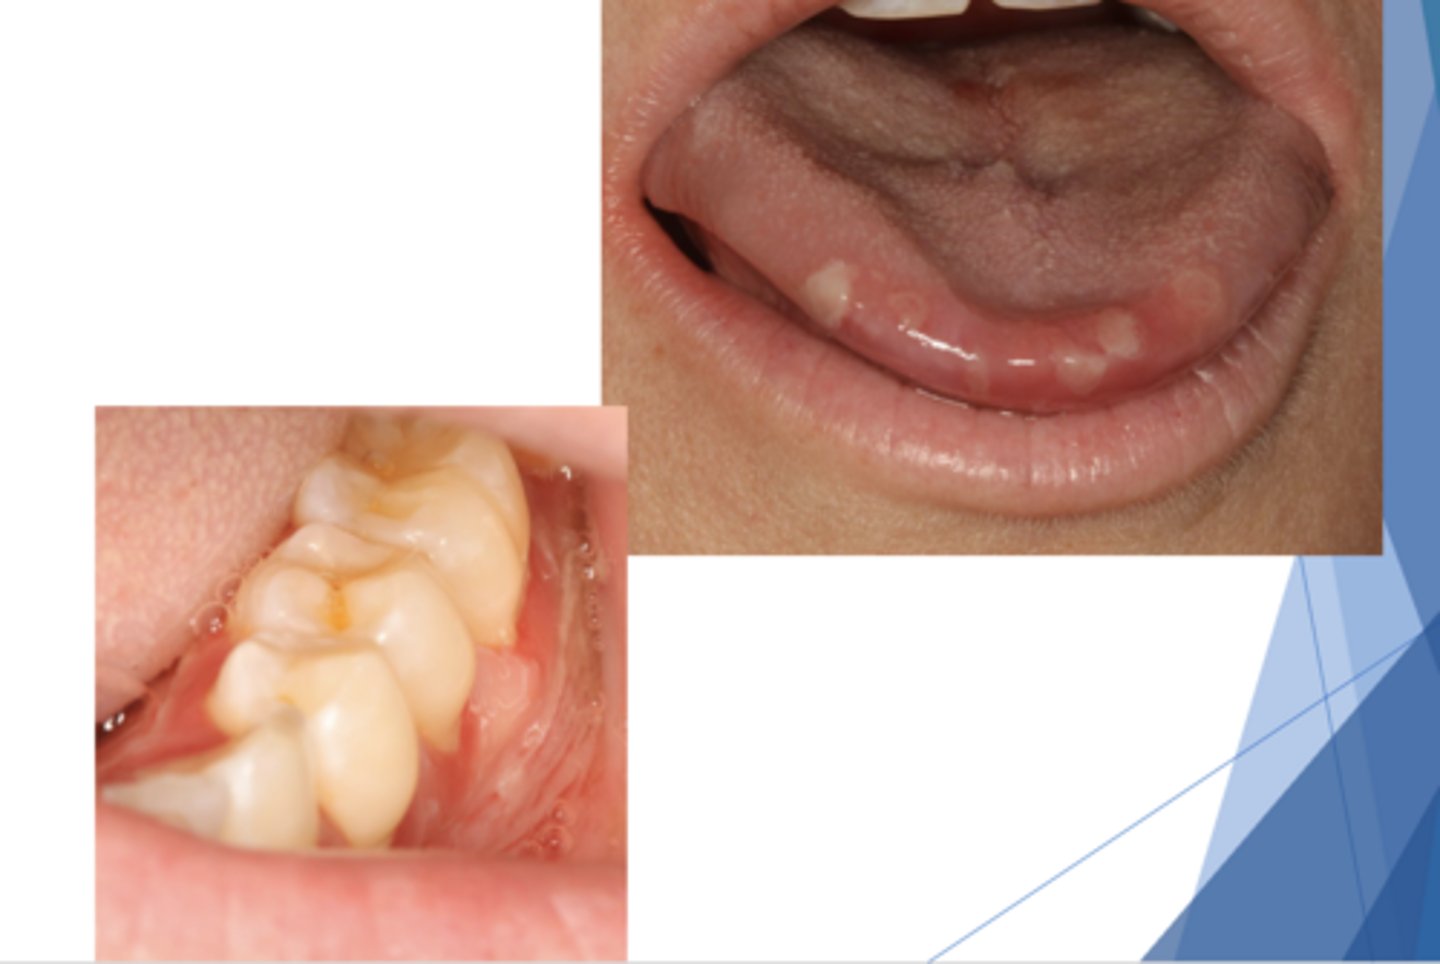

Graft vs. Host Disease (GVHD)

Patient presents with these oral lesions and recently received an allogeneic hematopoietic stem cell transplant. What is the most likely differential?